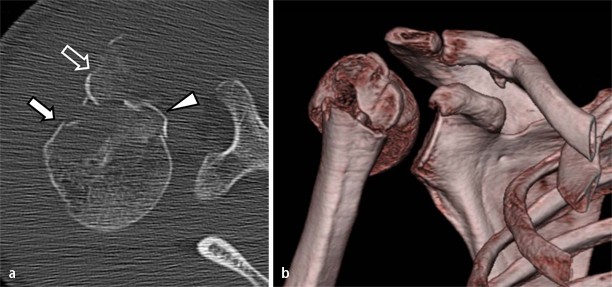

Kahnbein Fraktur Kahnbein Bruch Eine Einfuhrung

Das Who Is Who Der Extremitatenfrakturen Springerlink